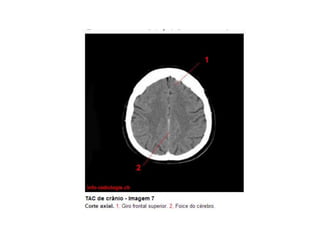

Anatomia E Protocolo Tomografia Computadorizada de Crânio PPT

Anatomia Seccional do Crâneo em Tomografia Computadorizada PPT